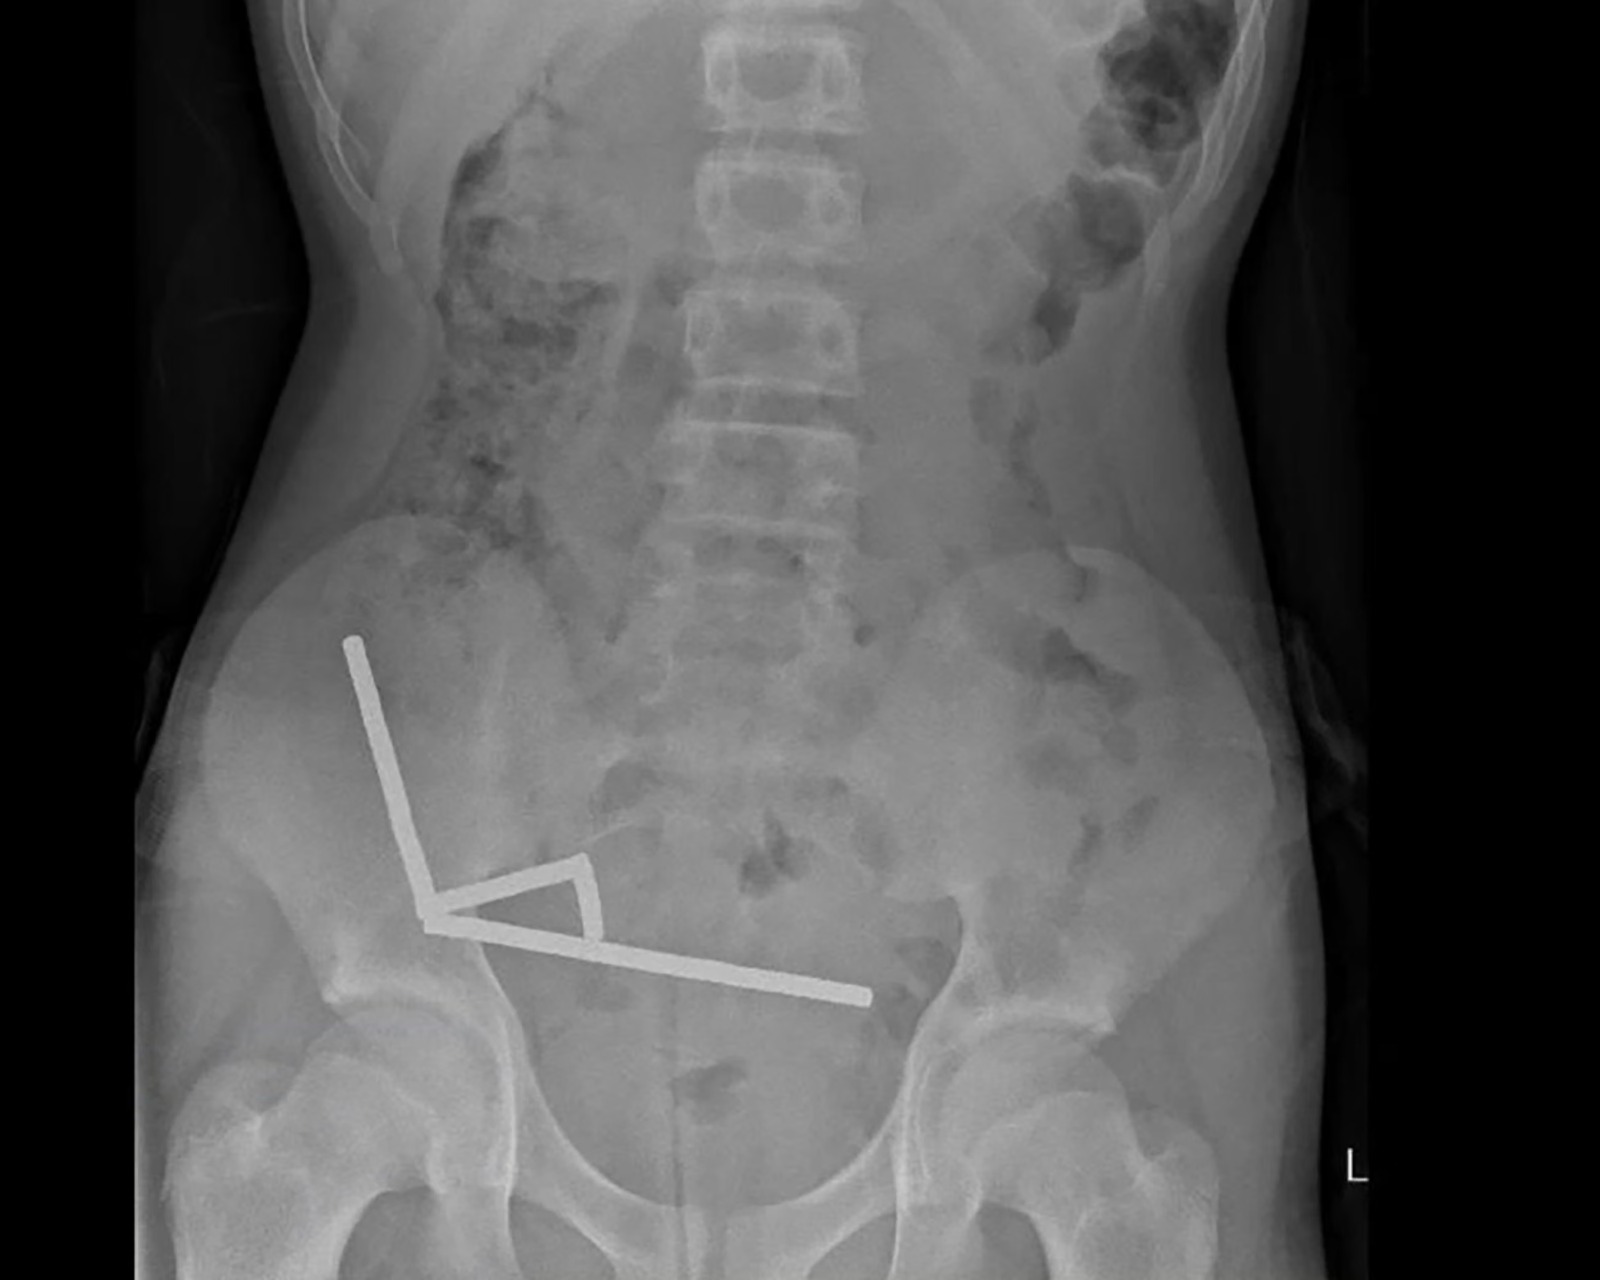

Un adolescente de 13 años en Nueva Zelanda se tragó 100 imanes de alta potencia que compró por Internet, lo que obligó a los cirujanos a extraer tejido de sus intestinos.

Tras cuatro días de dolor abdominal, el adolescente, cuyo nombre no se ha dado a conocer, fue trasladado al hospital de Tauranga, en la Isla Norte. «Reveló haber ingerido entre 80 y 100 imanes de neodimio de alta potencia de 5 x 2 mm aproximadamente una semana antes», según un informe de médicos del hospital publicado en el New Zealand Medical Journal.